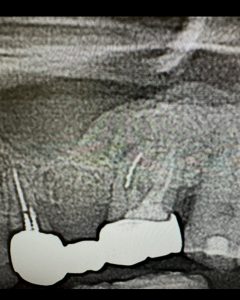

午後最終の方は他院での破折ファイルあり

その先には、病巣が大!

開けなければ、治らない、根切は侵襲大だからとにかく穿通さえすれば!